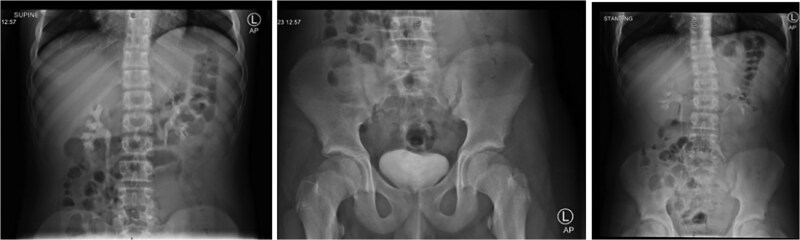

Castleman病是一种罕见的淋巴细胞增生性疾病,病因不明,其最常见的症状是纵隔淋巴结肿物。虽然它在年轻人中很少见,但在成年人中很普遍。我们报告一个病例14岁的男孩谁是入院的外科急性右侧腹痛,怀疑急性阑尾炎。术前腹部影像学检查显示炎性阑尾及大肠系膜肿块。经组织病理学检查证实为急性阑尾炎及单中心肠系膜肿块,经腹腔镜手术切除。

The most prevalent symptom of Castleman disease, a rare lymphoproliferative condition with an unclear etiology, is a mediastinal nodal mass. While it is quite uncommon in youngsters, it is prevalent in adults. We report a case of a 14-year-old boy who was admitted to the department of surgery for acute right-sided abdominal pain, with suspected acute appendicitis. Preoperative imaging investigation of the abdomen showed an inflammatory appendix as well a large mesenteric mass. Histopathology examination confirmed the diagnosis of acute appendicitis and mesenteric mass unicentric Castleman after resection by laparoscopic approach.